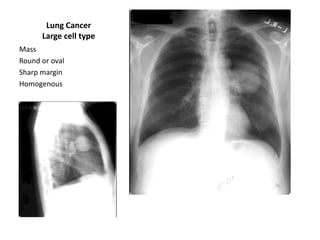

Lung Cancer

Large cell type

Mass

Round or oval

Sharp margin

Homogenous